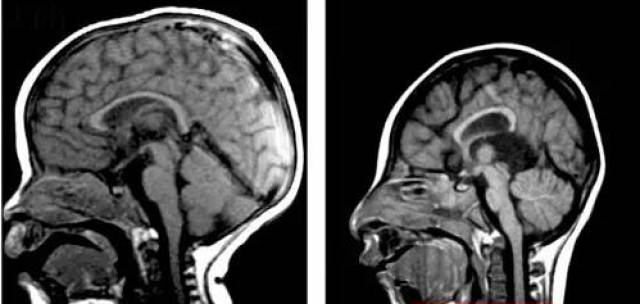

正常人的头颅()和小头症患者的头颅()对比,小头症患者的头颅明显小于常人,完全发育后头围也不超过42厘米。